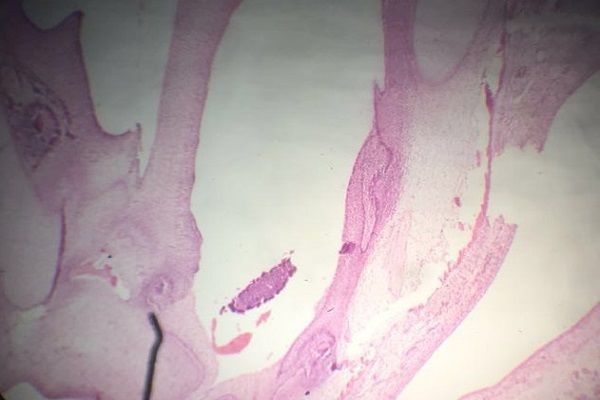

Question 3

Question

Label this image

Image:

6eeff475-4763-457e-a546-bc0f8ac946e8 (image/jpeg)

Answer

Embryonic Tooth